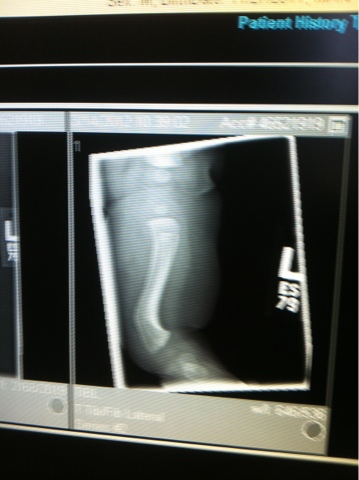

Ok I am probably just being dramatic but my little one had to be casted today. We got X-rays done 2 months ago and his leg was at a 45 degree bow. The X-rays today show the same. His body is not correcting it quick enough. The cast will help his leg grow straighter from now on...hopefully. The doctor wants to do 4-6 casts that are changed every 2 weeks. Hopefully he will get used to this extra baggage for the next few months. If this doesn't work he will have to have a surgery where they break his leg and reset it straight.